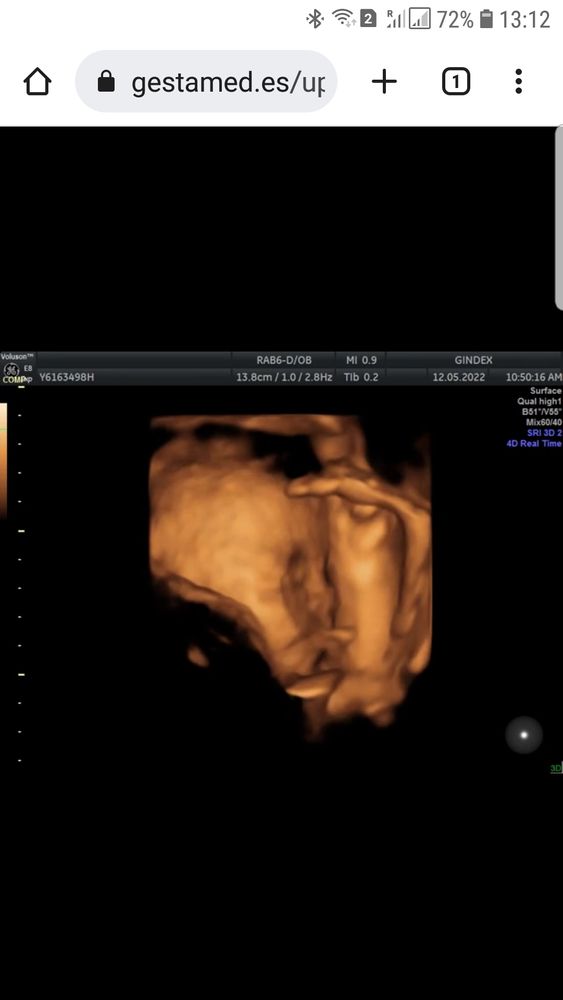

Весим мы сегодня 1,580кг и на узи личико активно закрываем и ножки поднимаем ☺☺. Да еще и доктор сегодня подтвердил, что будем делать кесарево, а я очень кесарево хотела. Такой у нас сплошной позитив